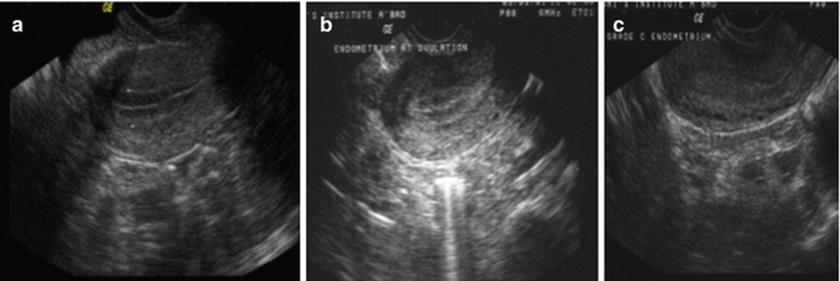

The morphology of the endometrium in the different phases of menstrual cycle is illustrated below (Fig. 2.17).

Fig. 2.17

Morphology of endometrium in the different phases of menstrual cycle. (a) Preovulatory, (b) at ovulation, (c) post ovulation

· Early proliferative phase – translucent and thin on either side of mid-line echo

· Late proliferative phase – increase in thickness with a hyporeflective area in the center

· Following ovulation – shrinks in thickness, becomes dense echogenic on either side of mid-line echo